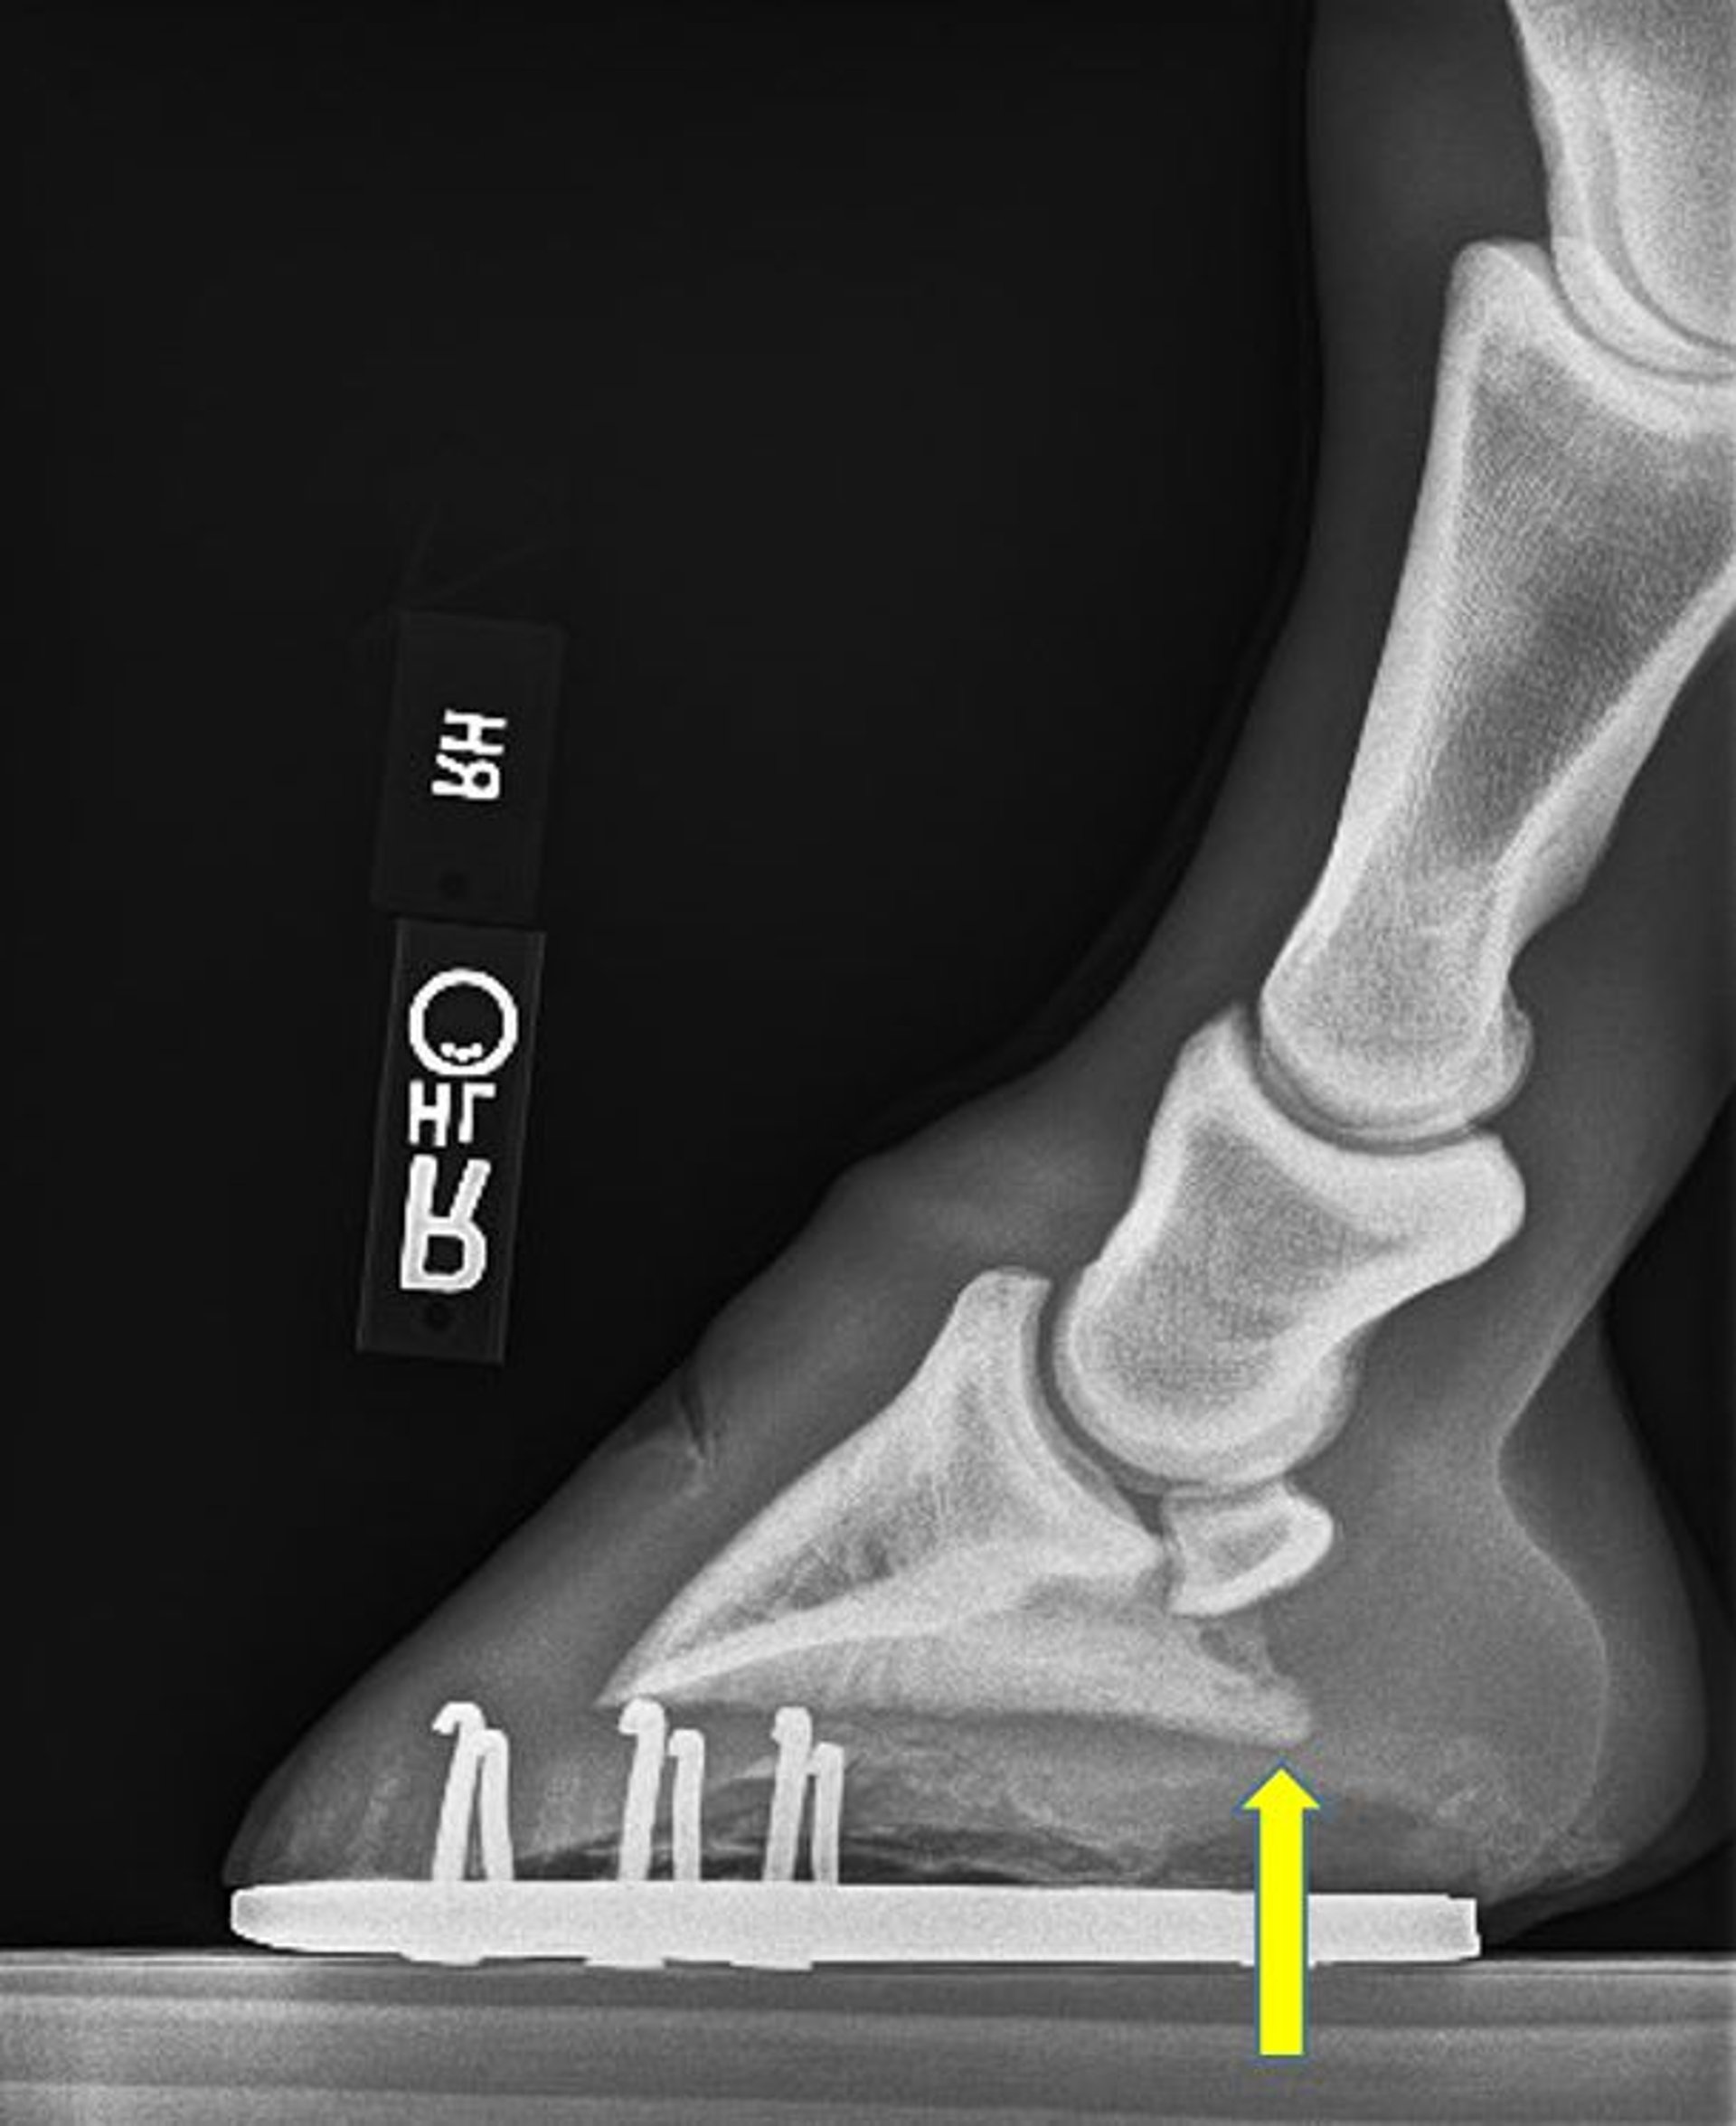

Radiografía lateromedial que muestra un desequilibrio sagital común del casco, también denominado ángulo palmar/plantar negativo, en un caballo. Obsérvese que en el margen solar, el aspecto palmar de la falange distal (flecha) es más distal que el aspecto dorsal.

Cortesía de la Dra. Valerie J. Moorman.